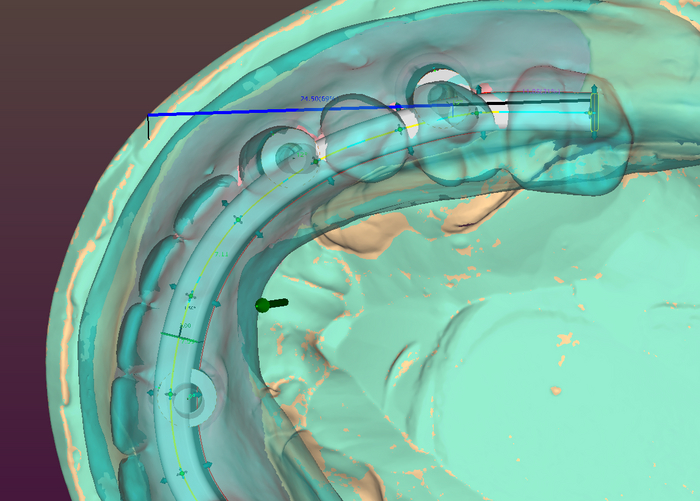

Балку получил из фрезерного центра, теперь надо её проверить на качество "посадки" на аналоги имплантов и в случае если будет баланс припассовать.

Титановый каркас "сидит" как надо не качается и не балансирует; не только на лабораторной модели, но и в полости рта — можно продолжать.

Далее проверяю если не нарушилось положение зубов при переносе, моделирую форму десны будущих протезов, снимаю при помощи технического силикона формы в которые заливается пластмасса.